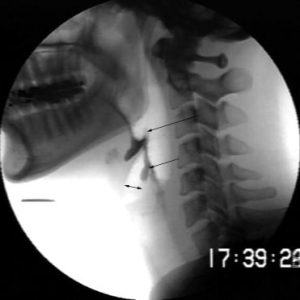

Enfermedades Cerebrales

Información sobre enfermedades cerebrales desarrollada por los profesionales especializados en neurorrehabilitación de Irenea, Instituto de Rehabilitación Neurológica de Vithas